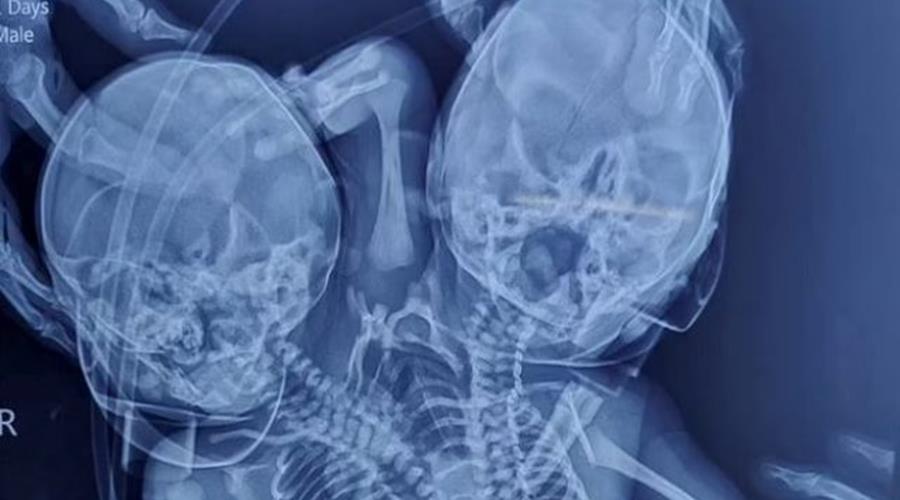

Πρόκειται για μια σπάνια περίπτωση

Η διαταραχή αυτή είναι γνωστή ως δικέφαλος parapagus dicefalik